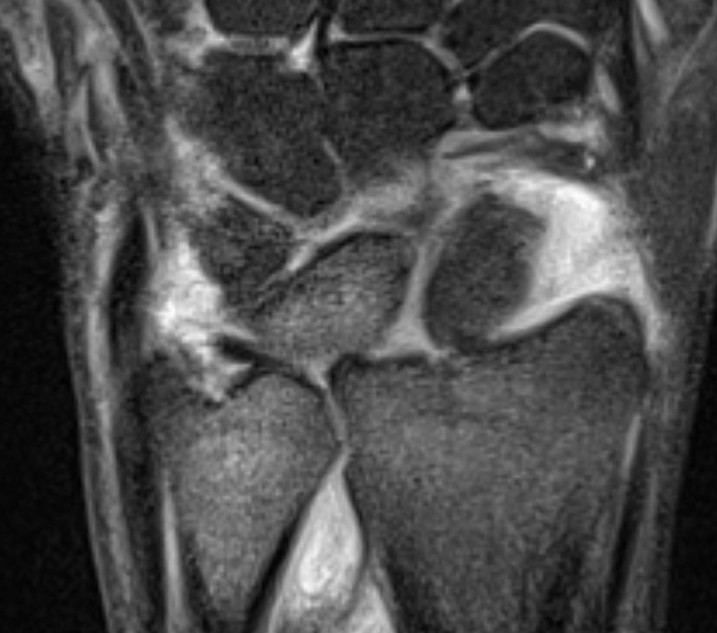

Ulno-carpal abutment

Ulnocarpal abutment and lunate chondromalacia

Ulna positive with ulnocarpal osteoarthritis

Class 2 Degenerative TFCC tears

Central TFCC tear with ulna positive variance an ulnocarpal abutment on MRI

Ulna impaction syndrome / Ulno-carpal abutment

Progression of wear

- TFCC thinning

- ulna head and lunate cartilage wear

- TFCC perforation

- lunate-triquetral ligament injury

- ulnocarpal osteoarthritis

Usually associated with ulna positive variance and treated with ulna shortening